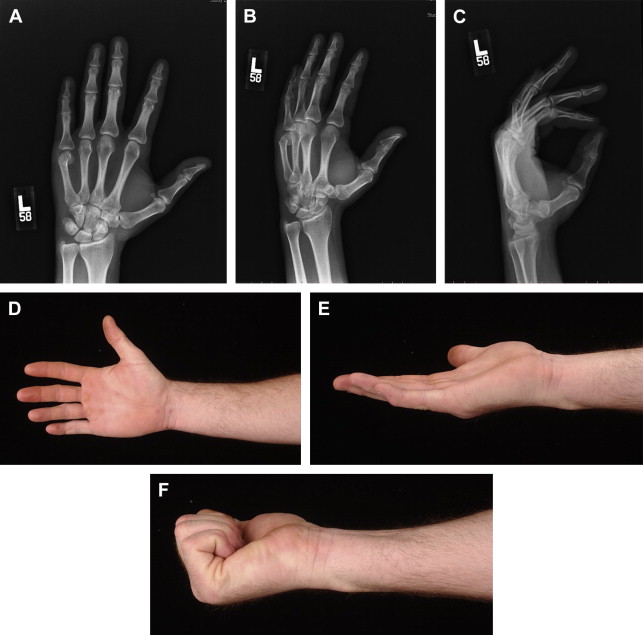

Fig. 1 illustrates a patient that sustained a third metalcarpal spiral fracture that had minimal displacement. The patient wanted surgery, believing it would restore normal function faster. The postreduction with rigid lag screw fixation revealed normal anatomic alignment. The postoperative course, however, was complicated with stiffness that necessitated formal physical therapy. Normal motion was finally obtained but somewhat prolonged (see Fig. 1 ). Similar fractures can be treated conservatively with rapid return to full activities ( Fig. 2 ). Metacarpal neck fractures tolerate conservative management extremely well ( Fig. 3 ). Even metacarpal shaft fractures can be treated in a conservative fashion despite significant dorsal angulation ( Fig. 4 ). These patients must initiate aggressive early motion to maintain normal function. The dorsal hump is usually cosmetic and does not foster physical limitations. Occasionally a palmar prominent metacarpal head can cause tenderness on gripping objects, but this is also uncommon. Multiple metacarpal fractures can also be treated nonoperatively with early active motion ( Fig. 5 ). The key to success is demonstrating normal motion with no scissoring or malalignment and regular follow-up visits. What defines stability of a fracture is an interesting concept. Fractures can be significantly displaced and considered unstable yet still heal with normal function with a conservative approach ( Fig. 6 ). Clinical studies defining the extent of the displacement that will compromise healing or function still need to be done.